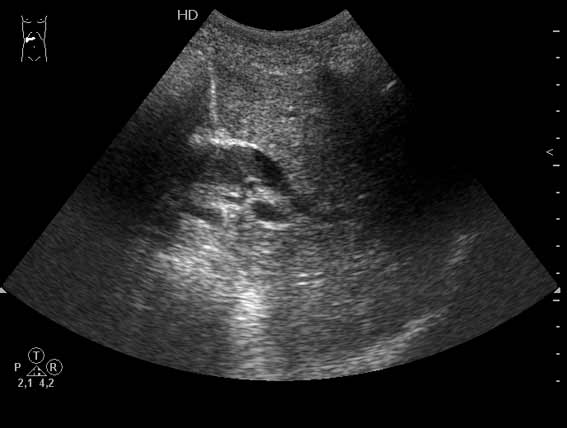

Очень пожилая женщина, обратилась в стационар из-за появления желтухи. Периодически беспокоили боли в эпигастрии и правом подреберье.

Желчный пузырь удален по поводу ЖКБ лет двадцать назад.

Не могу сказать что я вижу камень в холедохе на представленных сонограммах. Холедох расширен; интра-печёночные жёлчные пути тоже (значит прошло > 3 недель от момента обструкции). Жалоб на сильные приступообразные боли я не прочёл. Всё таки буду думать сначала о опухоли (если при УЗИ не нашли камня); рекомендация-таргетное КТ печени и поджелудочной.

Дело в том, что в холедохе имеется нечто изоэхогенное (не знаю, видно ли это нечто на ваших мониторах). Врач УЗИ при осмотре перед поступлением в стационар на основании этой картины в заключении отметил возможность опухоли холедоха.

Гнойный холангит на фоне обструкции БДС конкрементом (камень вне скана). В холедохе определяется желчь с осадком, которая может быть ошибочно принята за его опухоль.